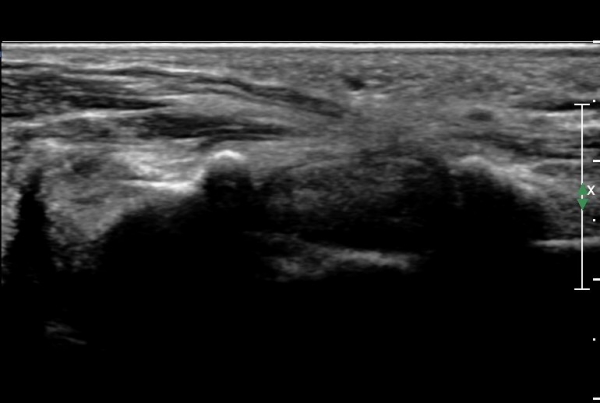

Á¤Á߽Űæ Á¾´Ü¸é°Ë»ç»ó ¼ö±Ù°ü ¸»´Ü(trapezium, capitate level)  µÎ²¨¿öÁø È¾¼ö±ÙÀδë(transverse carpal ligament)¿¡

ÀÇÇÑ Á¤Á߽ŰæÀÇ ±¹¼ÒÀû ¾Ð¹ÚÀÌ °üÂûµÊ(»çÁø 4, 5).